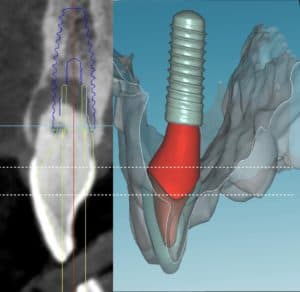

The main idea behind the static CAIS is rather simple: create an acrylic “template”, which will guide our drills to the perfect osteotomy and then place the implant accordingly. It is based therefore on a 3D printed surgical guide with “sleeves”, which allow the placement of the drills controlling angle and position and “stops” to control the depth. The guide can be supported on teeth, on oral mucosa, on the underlying bone through mini screws or a combination of the previous. It can be a single piece guide, or “stackable” in order to cover several procedures, such as for example a possible ostectomy prior to implant placement or a lateral sinus floor augmentation. But this is about where the principle ends and the application starts! Today almost every major implant brand has its own guided surgery software, instruments and overall protocol (Figure 2). The differences can be significant and this diversity is not based on evidence, but rather reflects each company’s philosophy, design, historical features and insider-view on implant surgery. Does it really matter? Well, evidence shows that it does. In a recent study we compared the precision of implant placement with 5 different commonly available guide designs and guided surgery configurations (3). The results showed significant differences, with the “sleeve in sleeve” guides achieving almost half the deviation than some of the “mounted” or “integrated” sleeve guides (Figure 2). At the same time, accuracy might be not the only parametre that is clinically important in a system. Ease of use by the surgeon, reliability of the full workflow, availability of a wide array of drills, sizes and components, durability and costs are also to be accounted for. As we begin to understand the implication of design parametres through proper research, guided surgery kits in the future might start to converge towards the best practices or principles which deliver the most. For now however, be mindful, there is not one such think as “static guided surgery protocol”, despite what some systematic reviews will try to convince you. On the contrary, there are many different protocols, with significant differences in results, potential and limitations. Choose wisely!